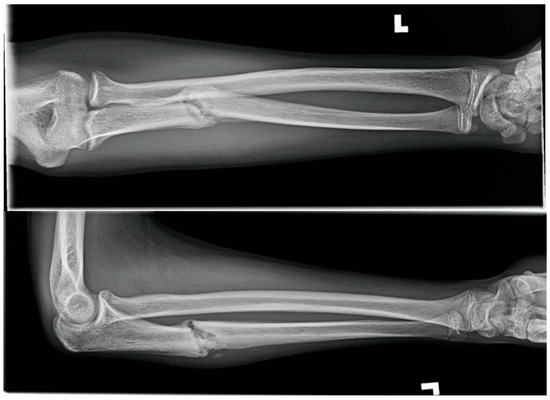

1.3. Forearm Fracture on a Trampoline, Eighteen Weeks in a 15-Year-Old Male

A fifteen-year-old male sustained closed, neurovascularly intact, displaced fractures of the radial and ulnar diaphyses with comminution of the radius. The mechanism of injury was a fall on an outstretched hand on a trampoline. The patient had no systemic comorbidity and no history of smoking but was a current user of electronic cigarettes. The fracture was splinted in a peripheral Emergency Room and was referred to our centre. The following day, the fractures were definitively treated without complication by open reduction internal fixation (ORIF) with plates and screws. The simple ulnar fracture was plated in compression mode, and the mildly comminuted radial fracture was approximated and plated in bridge mode.

Five weeks after operative treatment splint immobilization was discontinued, and a functional brace was applied. Eight weeks after ORIF, radiographs demonstrated bony union of the ulna but no union of the radius fracture despite anatomic alignment. The patient was counselled to discontinue EC use. Again, at twelve weeks, there was no union of the radius fracture and the patient had ongoing symptoms (Figure 3). Delayed union was diagnosed. Eighteen weeks after ORIF the patient had clinically improved, radiographs demonstrated bony union, and treatment was discontinued.

Figure 3.

Twelve-week radiograph of an operatively treated both-bones forearm fracture in a pediatric electronic cigarette user. The ulna is healed, but the radius is not.